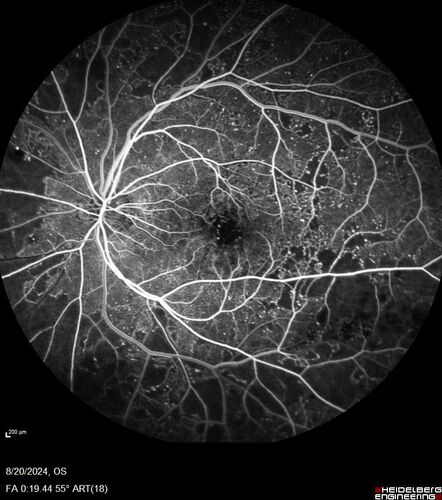

Severe NPDR with non-perfusion on FA

64 year old man with 20/32 vision in both eyes and mild blurring. FA shows non-perfusion but no proliferation